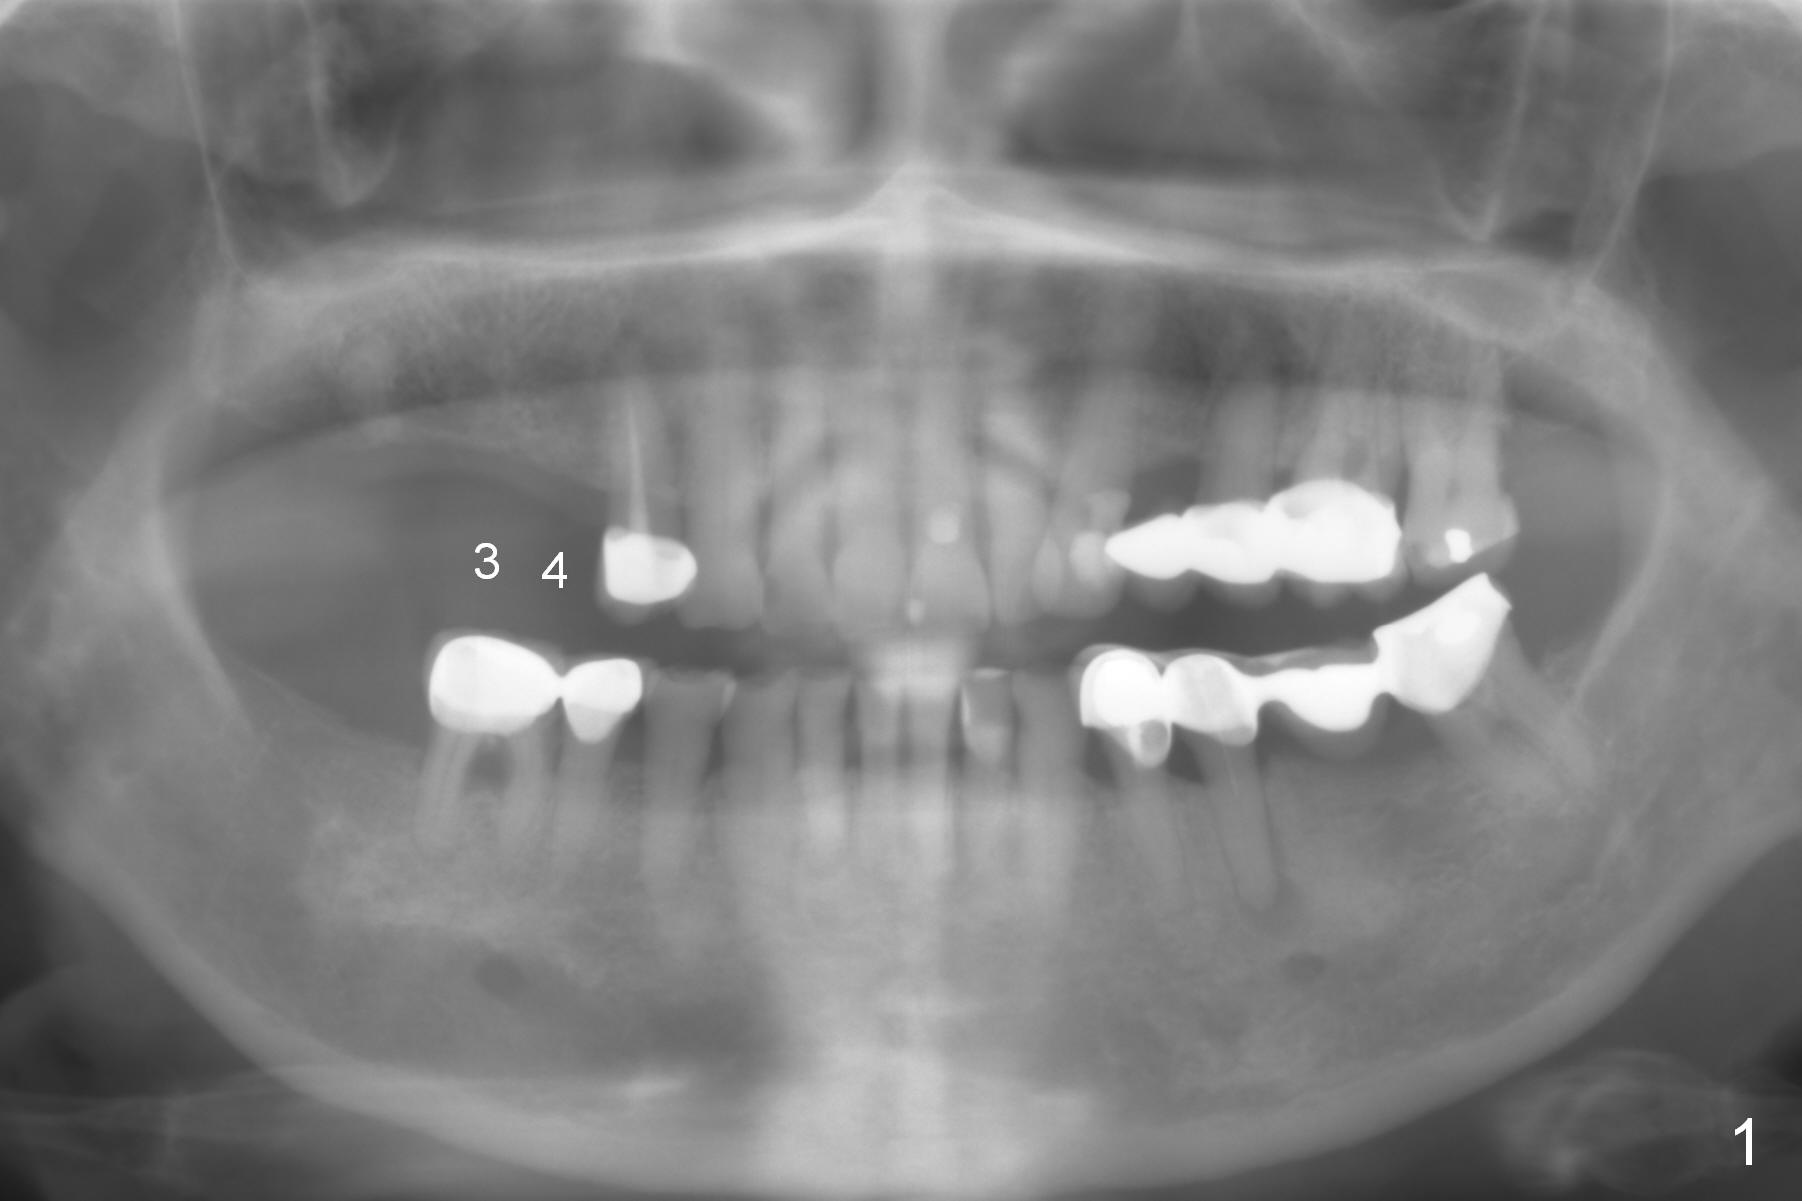

Improve Implant/Crown Ratio

A 78-year-old woman (possible osteoporosis) has poor dentition and restoration (Fig.1).  Implants will be placed at the sites of #3 and 4 with sufficient bone height as well as long edentulous vertical height (Fig.2).  To improve implant/crown ratio and assure primary stability, long implants will be placed: 16 mm bone-level.  Osteotomy is to be initiated through surgical stent with the longest Tatum 1.5 mm pilot drill, followed by incision, initial depth of 12 mm and PA.  If the bone proves to be soft, use DIO bone expansion kit and wheel splitter .  Splinted immediate provisional is going to be fabricated.  Surgical stents are available.